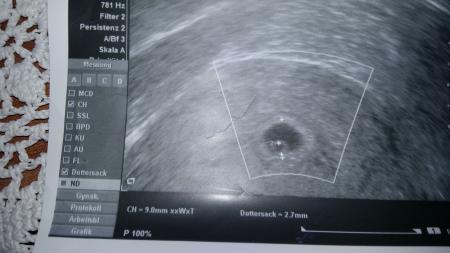

In welcher woche bin ich.????am 13.8 uns am 17.9 regel. fruchthöhle und nur dottersack

Hallo Nadine 1980 schau mal hab da ne bildergalerie gefunden vieleicht hilft dir das ein wenig -ich würde fast sagen dubst nach dem Ultraschallbild zwische der 4. und 5 Ssw. http://www.onmeda.de/bildergalerien/bildergalerie_ultraschall_schwangerschaft.html Gruß MArtina